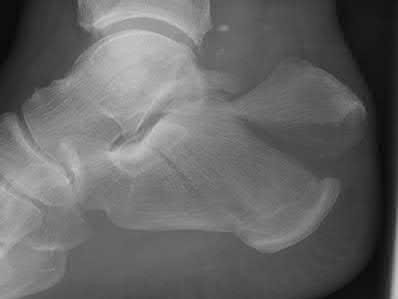

A 25-year-old female is involved in a motor vehicle collision. She presents with the isolated injury seen in Figures A through D. Her leg is swollen but her skin is intact. She has no clinical signs of compartment syndrome. Which of the following treatment options will allow for maintenance of fracture alignment and minimize the risk of soft tissue complications?

The patient presents with a closed distal third metaphyseal-diaphyseal distal tibia fracture with simple intra-articular extension. Immediate intramedullary nailing along with percutaneous fixation of the articular component provides appropriate restoration of length, rotation and alignment and minimizes the risk of wound complication.

Figures A and B demonstrate a distal third tibial shaft fracture with simple intra-articular extension. The axial and coronal CT cuts in Figures C and D further clarify the articular injury. Illustrations A and B demonstrate a comminuted distal third tibial fracture with simple intra-articular extension. Illustrations C and D are fluoroscopic images of the same injury after intramedullary nailing and percutaneous fixation of the articular component.